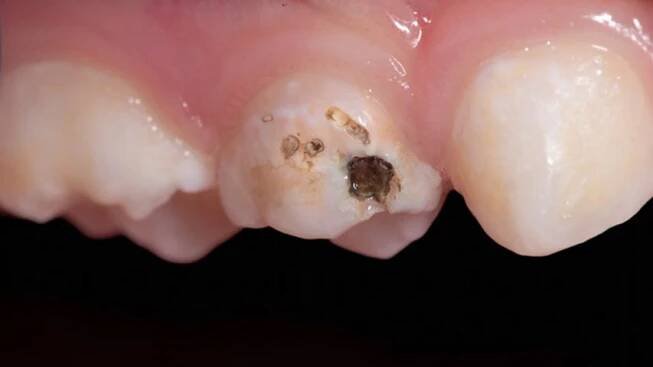

Zachraň mléčnou pětku: 3.díl kaz na žvýkací plošce

Fotka s případovou studií před-po. Na první force je vidět zub s nezaplněným kořenovýcm systémem a na druhé je vidět zub s dokonale zaplněným kořenovým systémem.